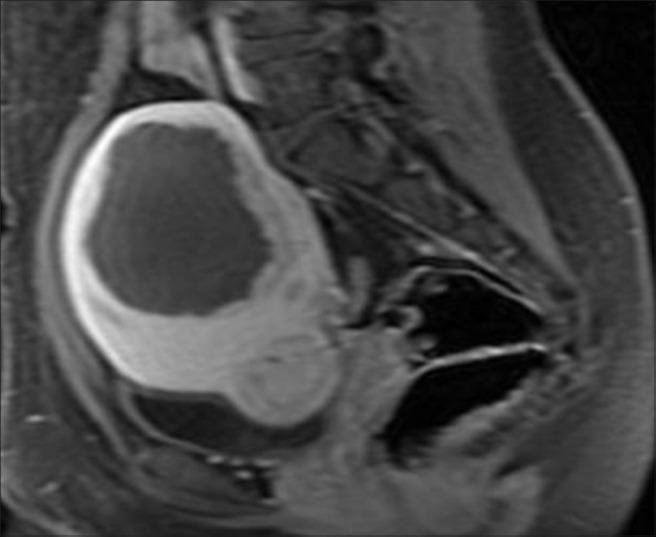

Fifty Indian women (mean age = 36.2 ± 8.3 years) were treated for fibroids as outpatients using the ExAblate MRgFUS system (InSightec). Non-perfused volumes (NPVs) were measured immediately after treatment to calculate the treatment outcomes. A validated symptom-specific questionnaire to record their symptoms prior to treatment and six months following treatment was completed by patients. The size of the fibroids was measured on the day of the treatment and during the 6-month checkup to calculate shrinkage. Adverse events during and following treatment were recorded and monitored.

The average NPV ratio measured after the treatment was 88% ± 6%, indicative of high ablated fibroid tissue. Prior to treatment, the mean Symptoms Severity Score was 56.9 ± 4.8 (n = 50), which is indicative of highly symptomatic patients. Six months following treatment, there was an average fibroid shrinkage of 30% ± 11%, and a significant decrease in the mean score to 28.6 ± 6.0 (n = 50) (P < 0.001). There were no reports of serious or unexpected adverse events at any point during treatment or during the follow-up period from any of the 50 women treated in the current study.

The current results obtained after 6 months of treatment corroborated previous data on the safety and efficacy of MRgFUS for treating uterine fibroids. This is the first publication that provides such data for a large cohort of Indian women.